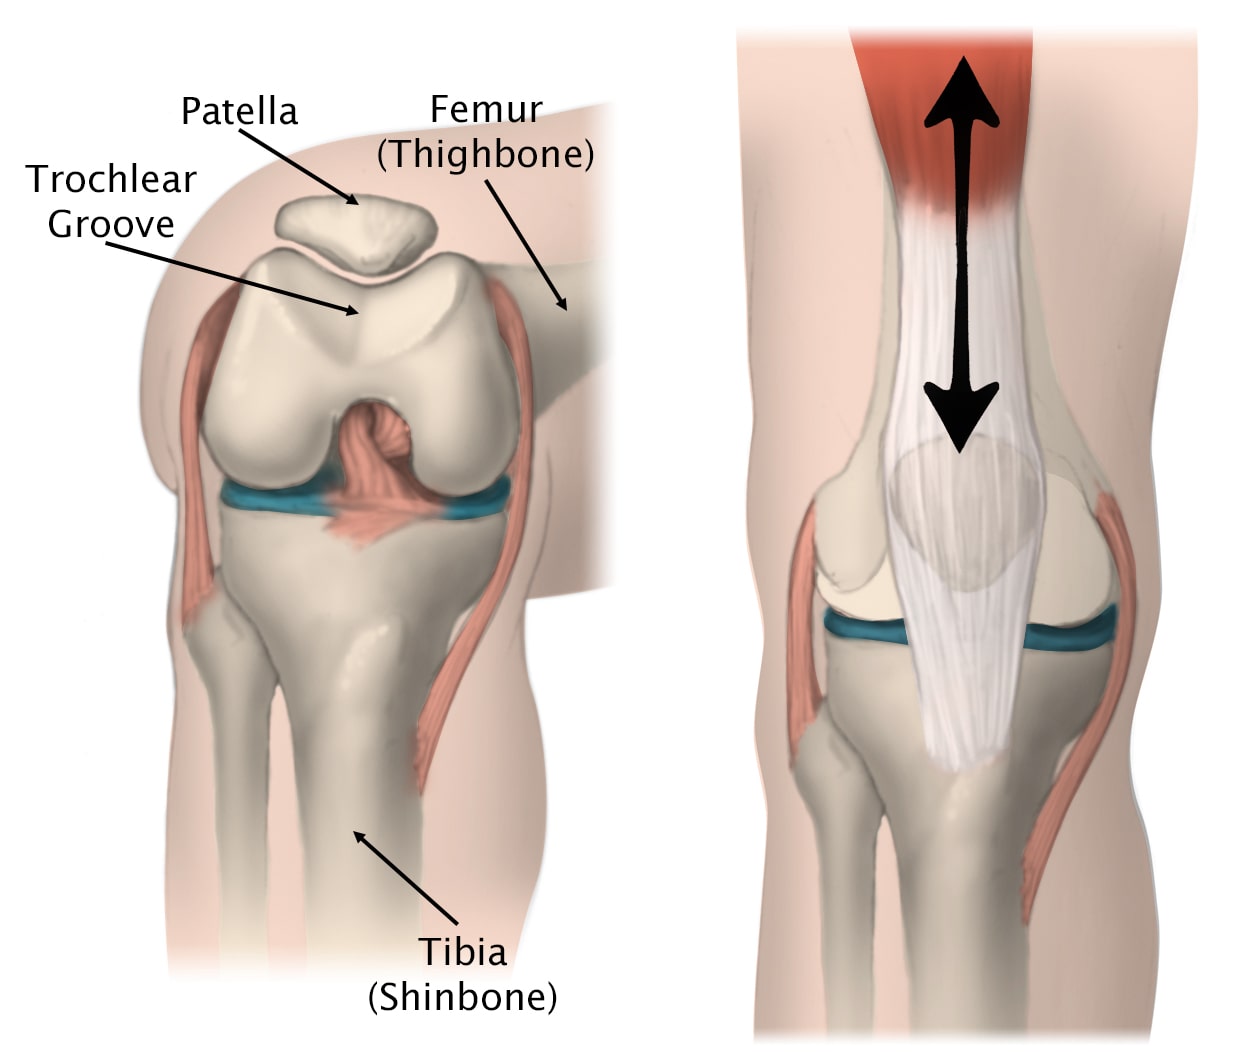

Several structures in the knee joint make movement easier. For example, the patella rests in a groove on the top of the femur called the trochlea. When you bend or straighten your knee, the patella moves back and forth inside this trochlear groove.

movement of the patella in the trochlear groove

(Left) The patella normally rests in a small groove at the end of the femur called the trochlear groove. (Right) As you bend and straighten your knee, the patella slides up and down within the groove.